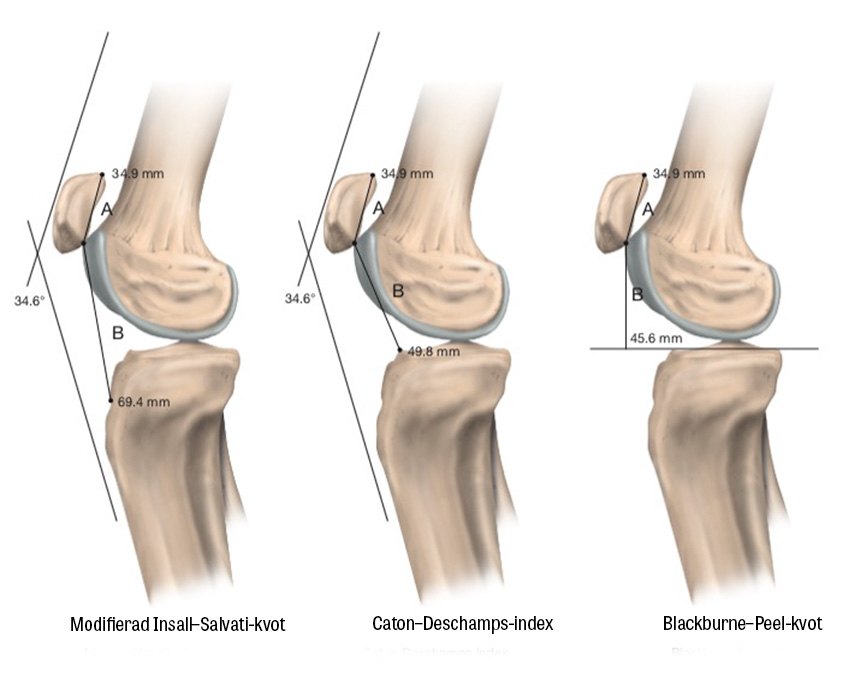

Patella alta. Utvecklingsrubbning där patella engagerar trochlea endast vid hög knäflexionsvinkel och i sin tur ökar risken för luxation.

Slätröntgen av knät bör omfatta tre projektioner: anteroposterior, lateral med knät i 30 graders flexion samt femoropatellär vy (Merchants vy) [11]. Subluxation, patellar tilt och trochleadysplasi värderas med Merchants vy, medan patella alta bedöms lättast med den laterala vyn.